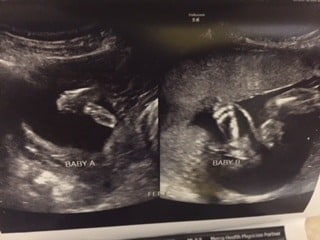

- Ultrasound Photos at 16 Weeks Pregnant With Twins

Ultrasound Photos at 16 Weeks Pregnant With Twins